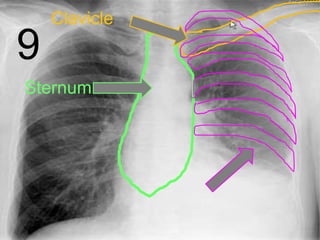

• Your skeletal system surrounds your most

important internal organs with a rib cage.